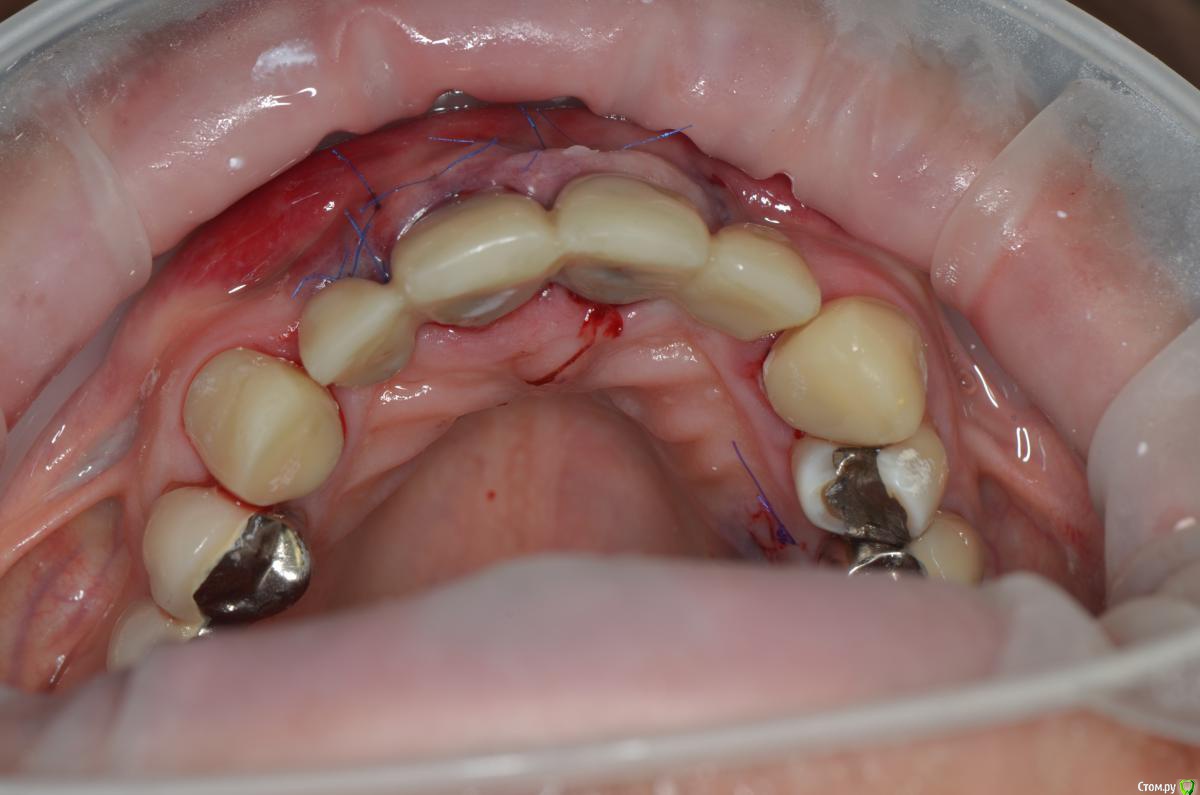

gangsta85 Опубликовано 27 сентября, 2016 Поделиться Опубликовано 27 сентября, 2016 Здравствуйте, уважаемые коллеги.Помогите пожалуйста разобраться.Центральные резцы в\ч были удалены и установлено 2 имплантата с пластикой десны, 12,22 отсутствуют в области 12 трансплантация слизистого лоскута.В тот же день изготовлены времянки по ключу с ваксапа. профиль трансгингивальной части сделан максимально под размер постоянной реставрации. 12,22 овоиды плотно прилегающие к десне.Вопросы:- Можно ли изготовить времянки сразу по форме максимально похожей на будущие реставраций и свести к минимуму коррекции профиля десны?- можно ли сделать надрез в области 22 и максимально погрузить в десну овоид 22, насколько плотно можно прижать овоид 11 в области слизистого трансплантата?- можно ли в такой ситуации добиться формирования десневых сосочков в области 12,22?-через какое время можно снять времянки для коррекции?- постоянная реставрация через 4 месяца? Что если снять слепок в день операции в лаборатории отфрезеровать времянки и установить через 1-2 дня , удастся ли в программе отмоделировать правильный профиль десны и овоиды? Как бы вы предпочли сделать времянки на CAD\CAM или в ручную? Ссылка на комментарий

ReaperGanzA Опубликовано 28 сентября, 2016 Поделиться Опубликовано 28 сентября, 2016 Имплантаты установлены с первичной стабильностью более 50н/см2.Временный протез выведен из окклюзии, перегрузки быть не должно.Клыки в прикусе, они имеют физиологическую подвижность, имплантаты нет, есть риск перелома времянок .Поправьте меня если рассуждаю неверно.Никто не предлагает вам объединять клыки и болты. Суть в другом.То что конструкция с центральными резцами в виде опоры и боковыми резцами в виде консолей имеет место быть, но в постоянной конструкции, а не в виде времянок для немедленной нагрузки.То что вы вывели времянки из центральной окклюзии я охотно верю, а вот то что вывели из переднего ведения и боковых экскурсий наврядле.Хирург конечно заинтересован в сохранении мягких тканей, но в данном случае с такой конструкцией это рискованно, особенно при наличии заточенных клыков. По-простому: после удаления поставить болты, заглушить, сделать мост с клыка по клык временный. На этапе раскрытия вкрутить титановые временные абатменты, отрезать от временного моста клыки, остальное перебазировать на временные абатменты, клыки зафиксировать и дальше работать с десной. Это более прогнозируемо 5 Ссылка на комментарий

ReaperGanzA Опубликовано 29 сентября, 2016 Поделиться Опубликовано 29 сентября, 2016 Спасибо за совет.Я вас понял, а если делать временный мост на клыки когда можно начать формирование десны?если хотите проще,то начать когда приживутся болты:1-вы не потеряете во времени так как попутно будете формировать контур прорезывания на болтах2-в зависимости от объема десны в области двоек вы сможете формировать овоиды компрессией ,либо пластикой десны красным шариком. В случае с компрессией лучше иметь прикрученный мост на болтах, чем мост на цементе на клыках, тк с цемента будет отваливаться. Более того вы в ходе прикручивания моста на болтах сможете контролировать ишемию десны и объем наращивания овоидов на двойках, и поддесневой части на центральных. Это удобно Ссылка на комментарий